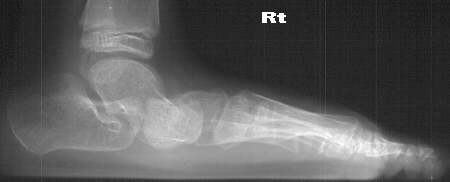

Radiographs reveal the following deformities:

- hindfoot valgus with AP talocalcaneal angle of > 35 degrees

- lateral subluxation/dislocation of the navicular from the talar head

- adduction of the metatarsals with the talus- 1st metatarsal angle to

be divergent medially

- increased lateral talocalcaneal angle with talus plantarflexed on calcaneus